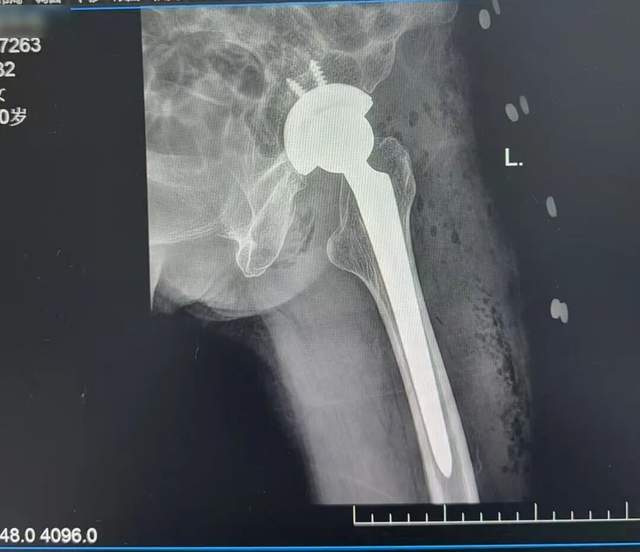

术后复查CT影像资料

由于刘阿婆本身患有慢性支气管炎和肺气肿,完善入院检查并请相关科室会诊协助诊疗后,排除了手术禁忌,在骨伤七科(关节病区)主任陈竹明的指导下,主刀的李岗副主任决定采用仰卧位直接前侧入路(DAA)。术中沿肌肉间隙进入,逐层分离、显露,适当松解、扩髓,安放合适假体。结合中医特色康复指导,患者术后第二天即可倚靠助行器下床活动,恢复迅速。这例手术的成功,展示了DAA技术在老年髋部骨折治疗中的显著优势。